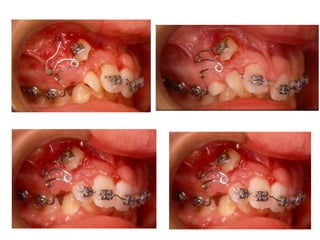

TRANSPOSIÇÃO TOTAL - CANINO COM INCISIVO LATERAL MANOBRAS PARA CORREÇÃO DA ROTA DE ERUPÇÃO